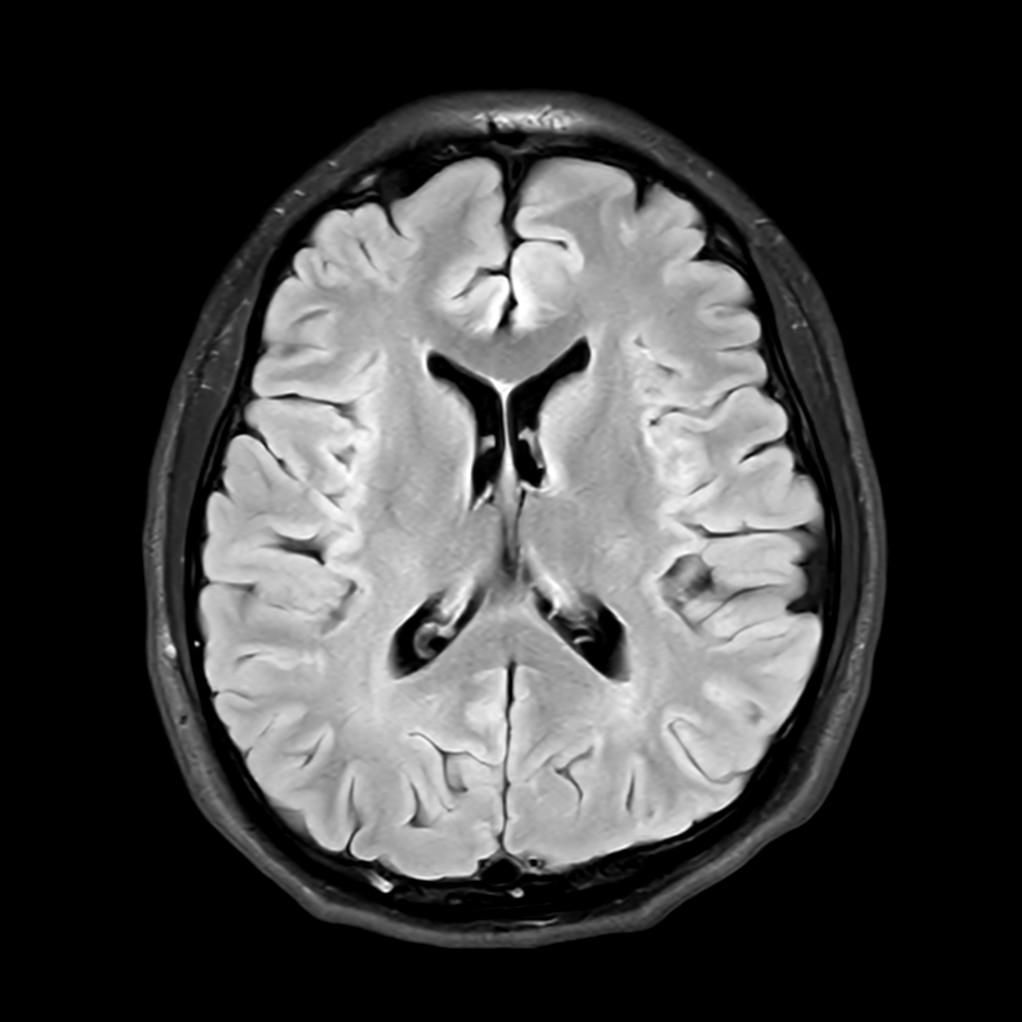

뇌 후두피질위축 봐주시면 감사하겠습니다(mri)

뇌의 위축 정도가 심한 상태인가요

요즘 눈이랑 정신이 좀 이상해서 뇌mri를 찍었는데 이렇게 나오네요.

알츠하이머와 관계가 있는 것 같은데..

정확한 것은 정식 판독을 받아보아야 알 수 있겠습니다만, 개인적인 경험을 토대로 보았을 때에는 위축이 심하다고 보기에는 무리가 있어 보입니다. 뇌실이 비정상적으로 커져 보이지도 않고 뇌의 태두리가 두개골에서 많이 떨어져 있지도 않은 것이, 해당 사진들만 보아서는 위축이 심하고 치매를 의심하여야 한다 어떻다 판단을 내리기는 어려울 것으로 사료됩니다.